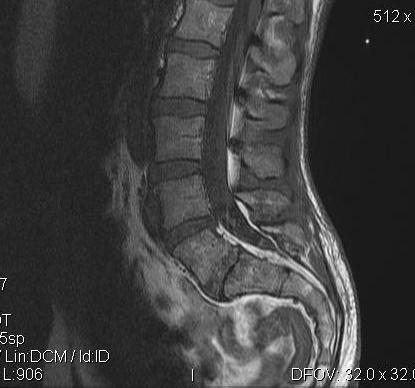

Lumbar Spinal Stenosis - Wikipedia

Lumbar spinal stenosis A physical therapy program to provide core strengthening and aerobic conditioning may be recommended. Overall scientific evidence is inconclusive on whether conservative approach or a surgical treatment is better for lumbar spinal stenosis. ... Read Article